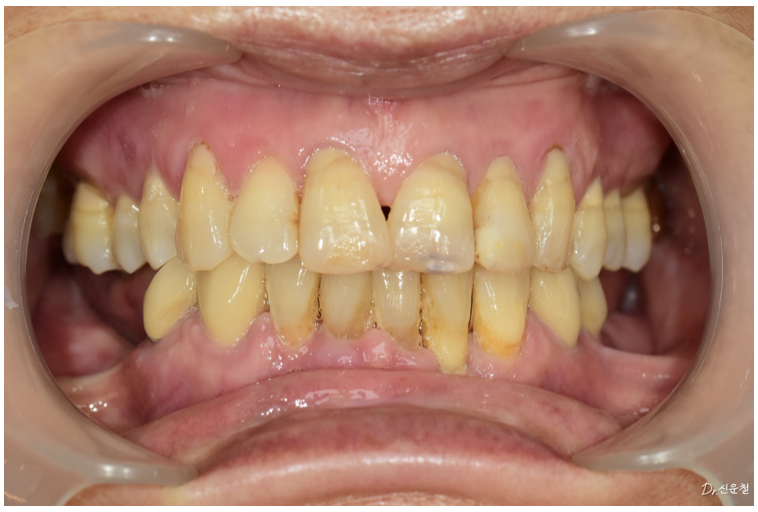

게다가 환자분은 기존 틀니도

착용감이 좋지 않다고 말씀하셨습니다.

그래서 단순히 틀니를 다시 만드는 것이 아니라

다른 방법이 가능한지도 함께 확인하게 되었습니다.